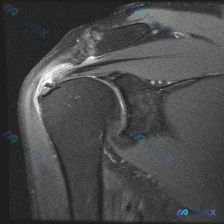

整理了一份肩部MRI病例讨论材料,医生的核心问题是排查盂唇病变,但看影像发现了一些矛盾点。先放MRI T2序列冠状位的分析: 1. 骨性结构:肱骨头、肩峰及锁骨远端轮廓尚可,未见骨折线或骨髓水肿 2. 肌腱与肩袖:冈上肌腱在肱骨大结节止点处形态异常,连续性中断,T2高信号 3. 关节与滑囊:肩峰下-...

最近整理了一份肩部MRI的病例讨论材料,患者主要问题是肩部疼痛,但问题明确指向"盂唇病变"范畴。先看T2冠状位图像的关键发现: 1. 冈上肌腱在肱骨大结节止点处有显著高信号,连续性可能中断 2. 肩峰下-三角肌下滑囊有明显的高信号积液 3. 关节盂唇区域信号存在改变 大家觉得这个病例更符合哪种诊断?...

看到一个肩部MRI(冠状位)的病例资料,用户最初的问题是关于「盂唇病理」,但整理的分析报告里有几个点挺值得讨论的: 先放影像的关键发现: - 冈上肌腱连续性中断,断端回缩,伴冈上肌肌腹萎缩、脂肪浸润 - 肩峰下-三角肌下滑囊积液,肩峰下间隙变窄,肱骨头上移 - 肱骨头大结节下方骨髓水肿 - 盂唇形态...

看到一个肩关节MRI病例资料,有个比较有意思的点:用户的问题是「What is the noticeable abnormality in this image?Labral pathology」(图像中明显的异常是什么?盂唇病变),但整理的影像分析报告核心发现是冈上肌腱全层撕裂。 先把报告里的关键...

看到一个肩关节MRI影像分析的病例材料,影像为冠状位T2加权图像,主要发现如下: 1. 冈上肌腱远端附着处全层撕裂,T2序列显示高信号液体填充 2. 肩峰下-三角肌下滑囊内有明显积液 3. 盂肱关节腔内有显著液体潴留 用户的核心问题是关于「盂唇病变」的可能性。这个病例有几个点值得讨论: - 冈上肌腱...